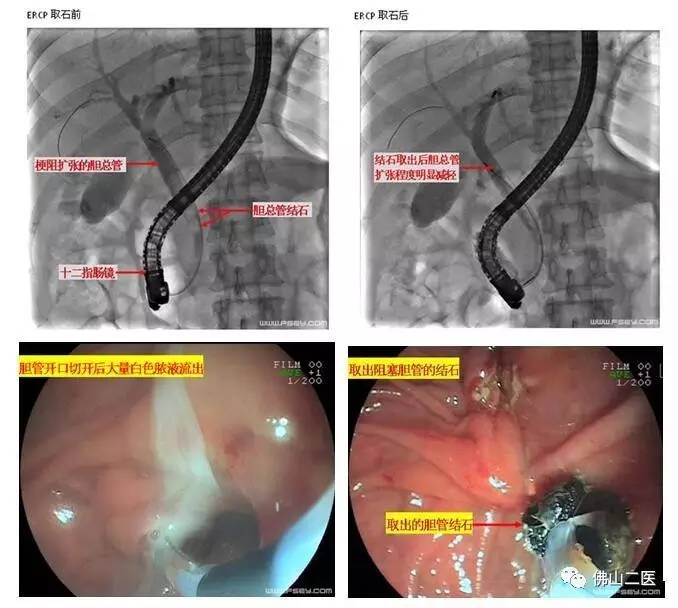

消化内科陈渭副主任医师紧急为患者进行了内镜微创治疗。内镜经过口腔、胃肠道到达胆总管开口,作了一个约半厘米长的小切口,引出大量脓液并取出堵塞胆管的多枚结石,治疗用时仅半小时。治疗结束时患者体温已下降至38℃,血压回升至110/80mmHg,腹痛也明显缓解。第二天黄疸就明显消退,恢复进食,现已康复出院。

ERCP是经内镜逆行胰胆管造影术的简称,因为可行切开、扩张、引流、取石等内镜下治疗操作,已成为胆胰疾病的重要微创治疗手段,也是目前公认的胆总管结石的首选治疗方法。目前我院消化内科已全面开展ERCP诊疗操作,可进行胆管结石、胆管癌、胰头癌、慢性胰腺炎等各类胆道、胰腺疾病的微创诊治,创伤小,恢复快,尤其适合不能耐受或不愿行手术治疗的患者,疗效显著,深得患者欢迎和认可。